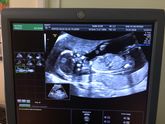

С малышаней все хорошо, наконец-то перевернулась и можно одевать бандаж!) моя прибавка ровно 10 кг, врач ругается, говорит разгрузочные дни устраивай и никаких булок и сладкого?? а доченька моя по весу 1650 грамм, сказали на недельку отстаёт, контрольное … Читать далее